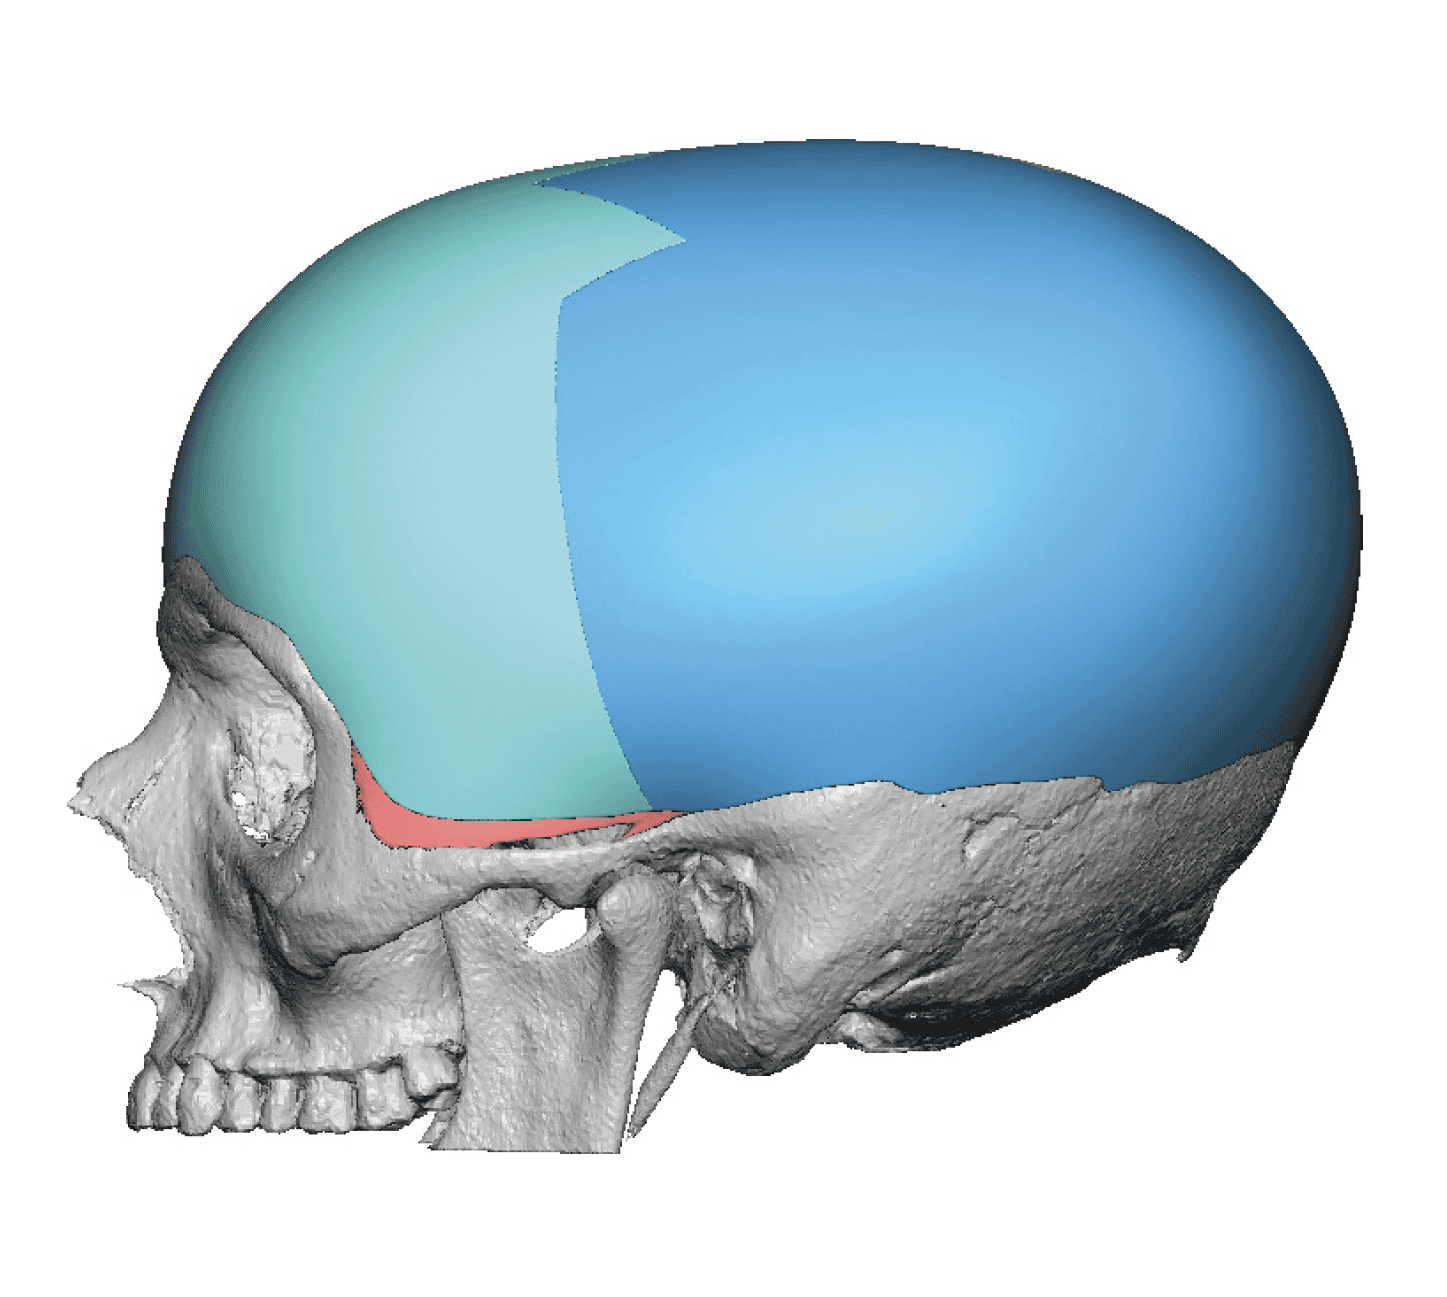

Placement of custom extended forehead-temporal implants through incisions in the crease behind the ear. (he had a prior back of head skull implant which is green in the implant designs and which the head widening implants partially covered it)

Desire for change of head shape from front view form an inverted V shape to a rounder and wider head shape.

Placement of custom extended forehead-temporal implants through incisions in the crease behind the ear. (he had a prior back of head skull implant which is green in the implant designs and which the head widening implants partially covered it)